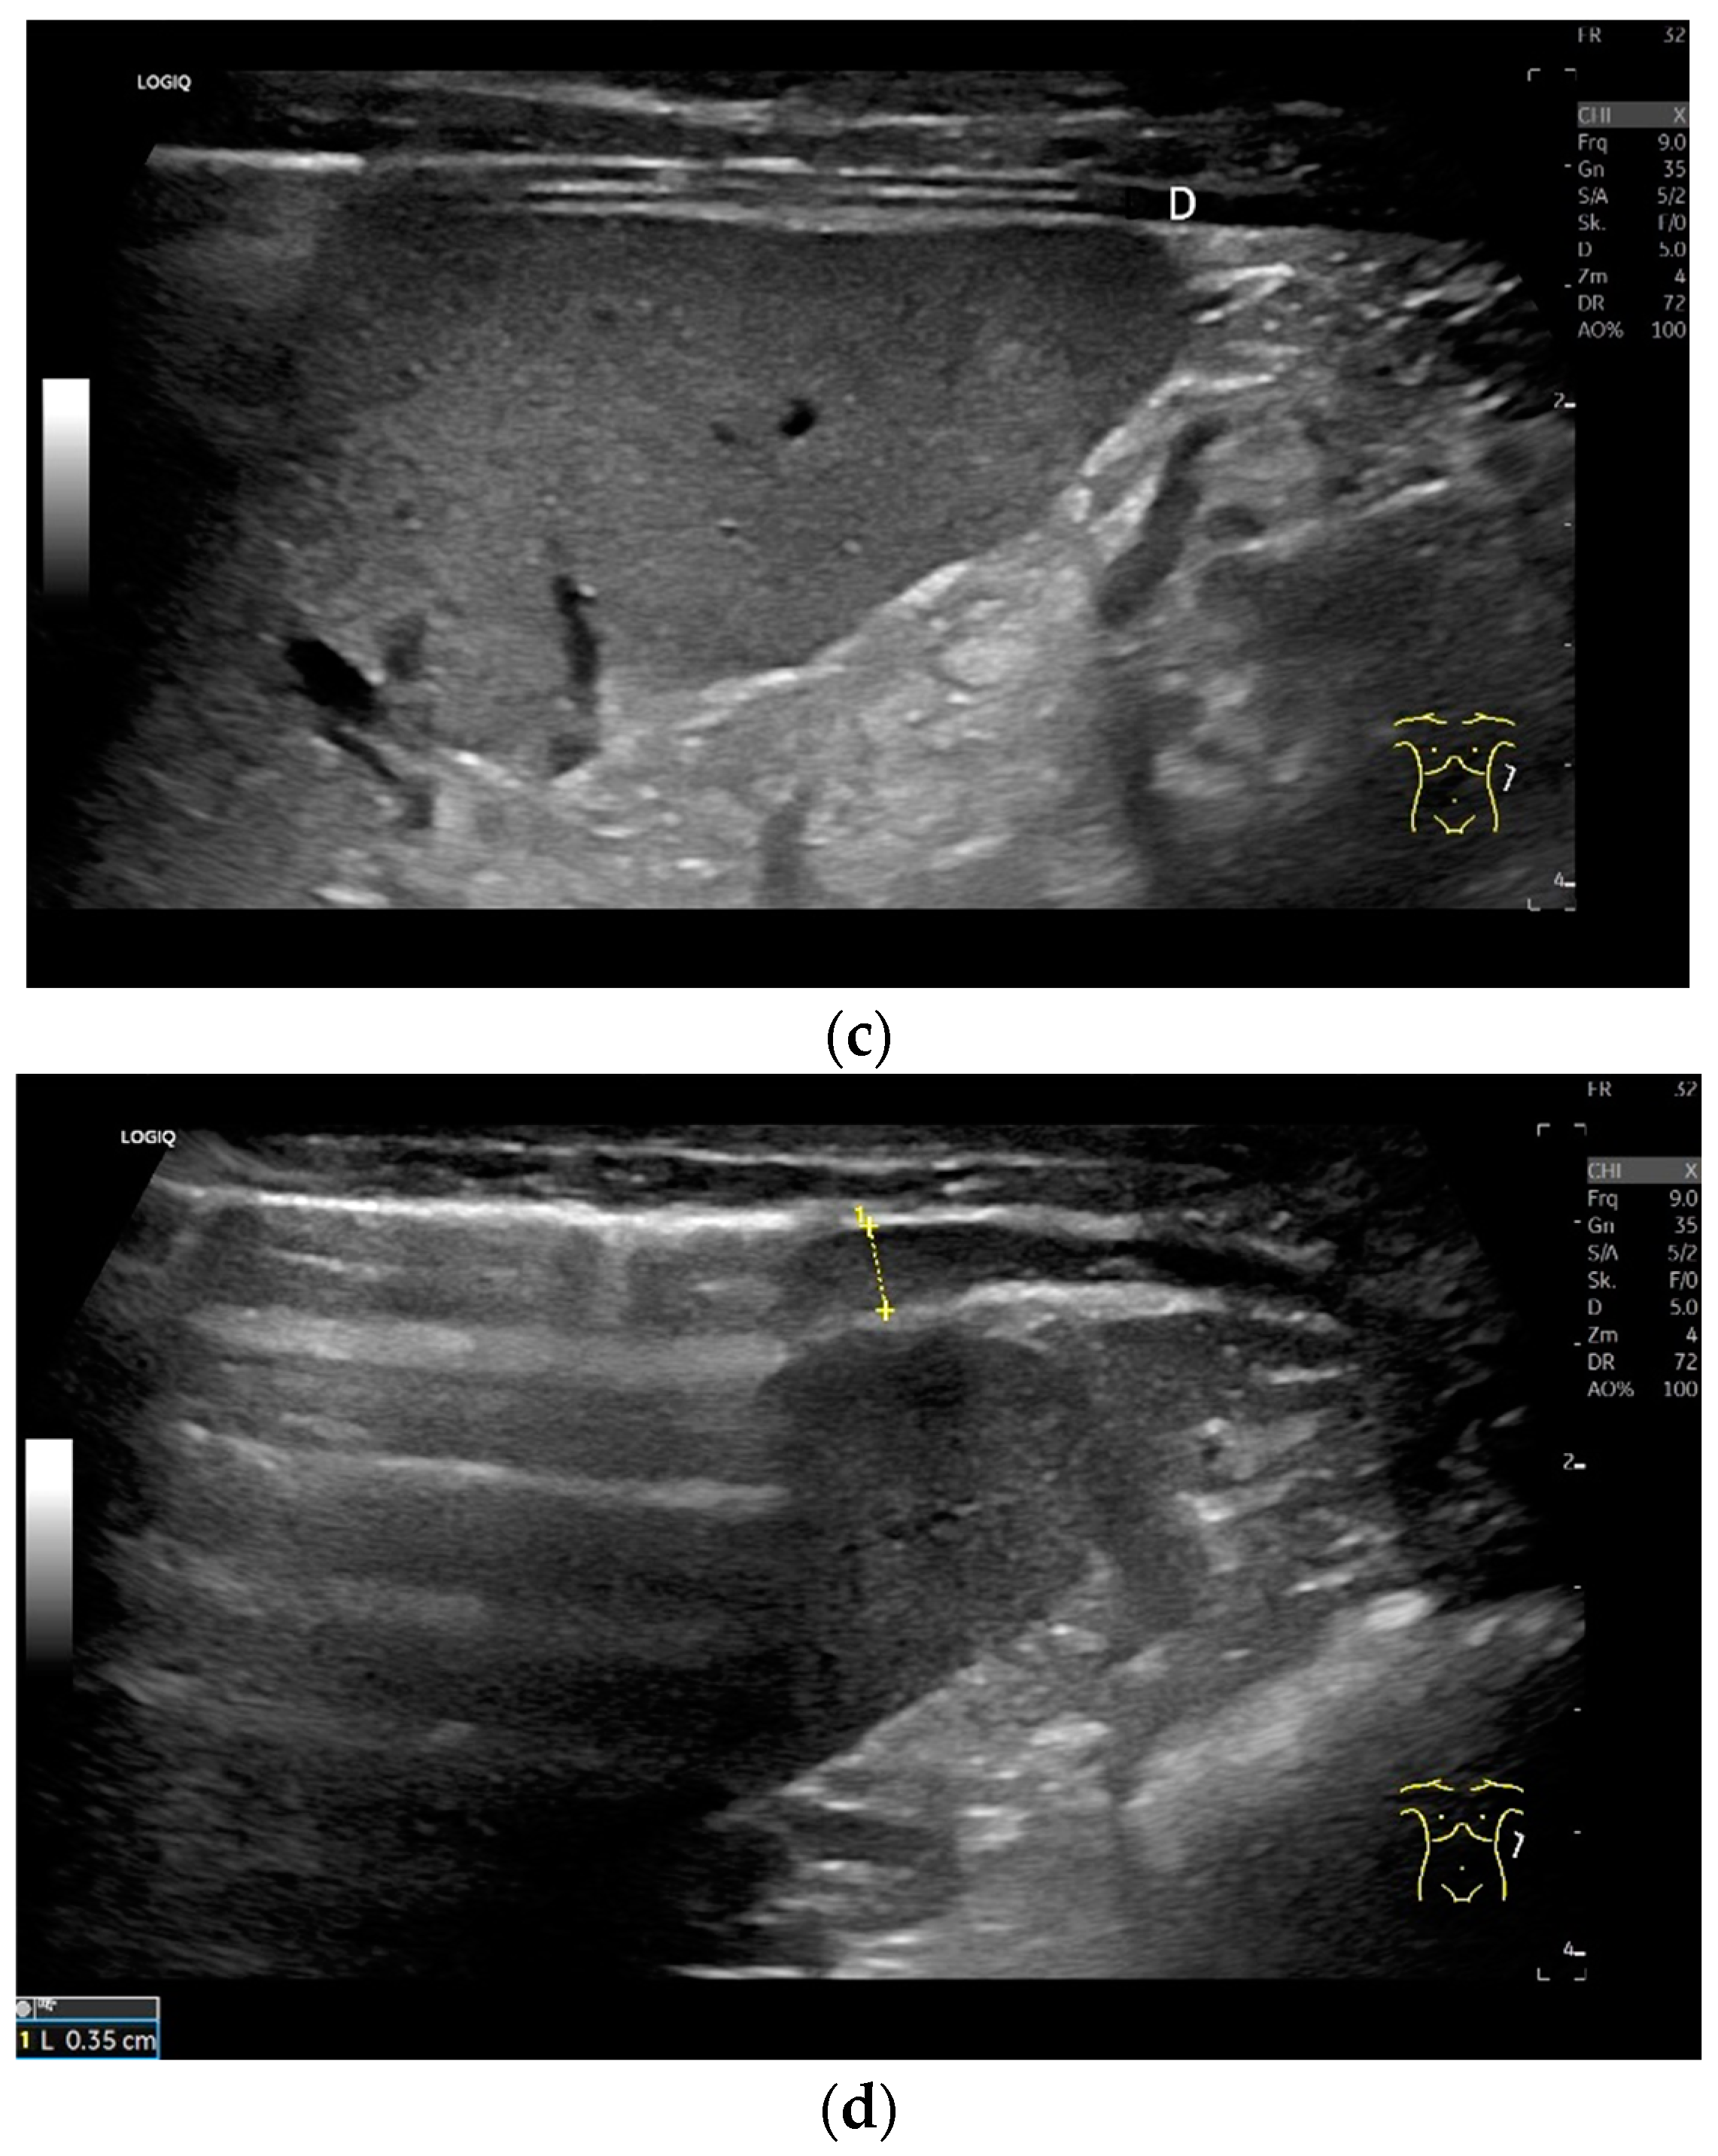

Subxiphoid: The diaphragm can be positioned directly subxiphoidally with a slightly sagittal transducer position on both sides next to the attachment to the sternum. The diaphragm limb can be demarcated to the right in the epigastrium in cross section between the aorta and the inferior vena cava. However, this is primarily of differential diagnostic importance, e.g., in relation to lymphomas, not for the actual assessment of the diaphragm (Figure 6).